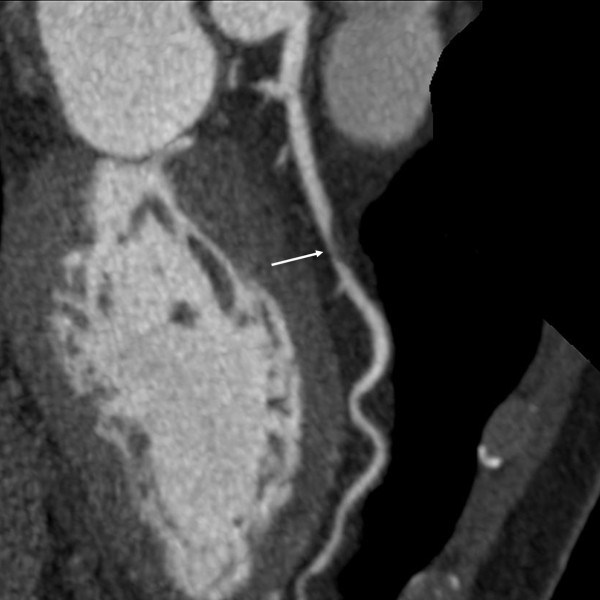

6.3 Sténoses coronaires

Le coroscanner évalue :

- le taux de rétrécissement luminal (en %),

- la localisation des sténoses,

- le nombre de vaisseaux atteints (mono, bi ou tritronculaire),

- l’aspect de la plaque responsable (molle, calcifiée, mixte).

- Calcifications massives : les artefacts de blooming peuvent gêner la visualisation de la lumière et réduire la spécificité.